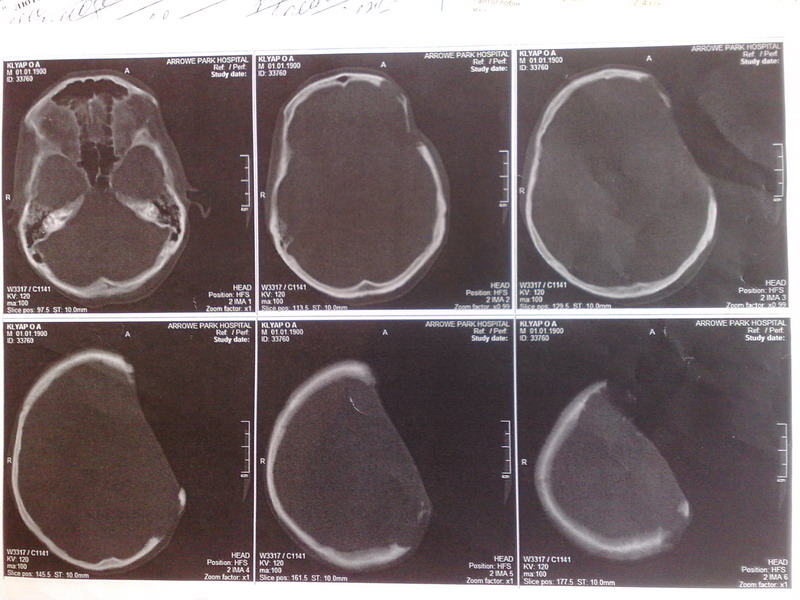

За последний год дефект немного увеличился. Несколько дней назад было сделано КТ на котором

поражения головного мозга не обнаружено. Додаю результаты КТ.